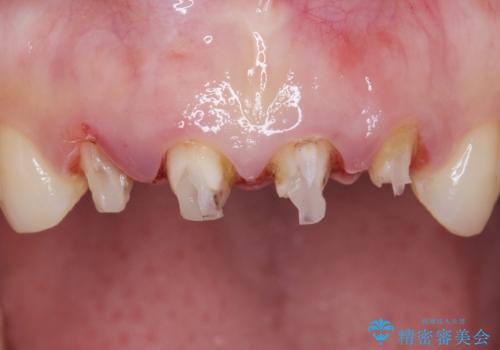

歯茎の腫脹が顕著であったため、適合の良いオーダーメイドの仮歯に変え、歯茎の状態が良くなるまで1ヶ月待ったのち型取りを行いました。

自然な仕上がりに大変喜んで頂けました。

単冠かつ適合の良いクラウンにより清掃性が良くなり、歯茎の腫れ・出血もなくなりました。